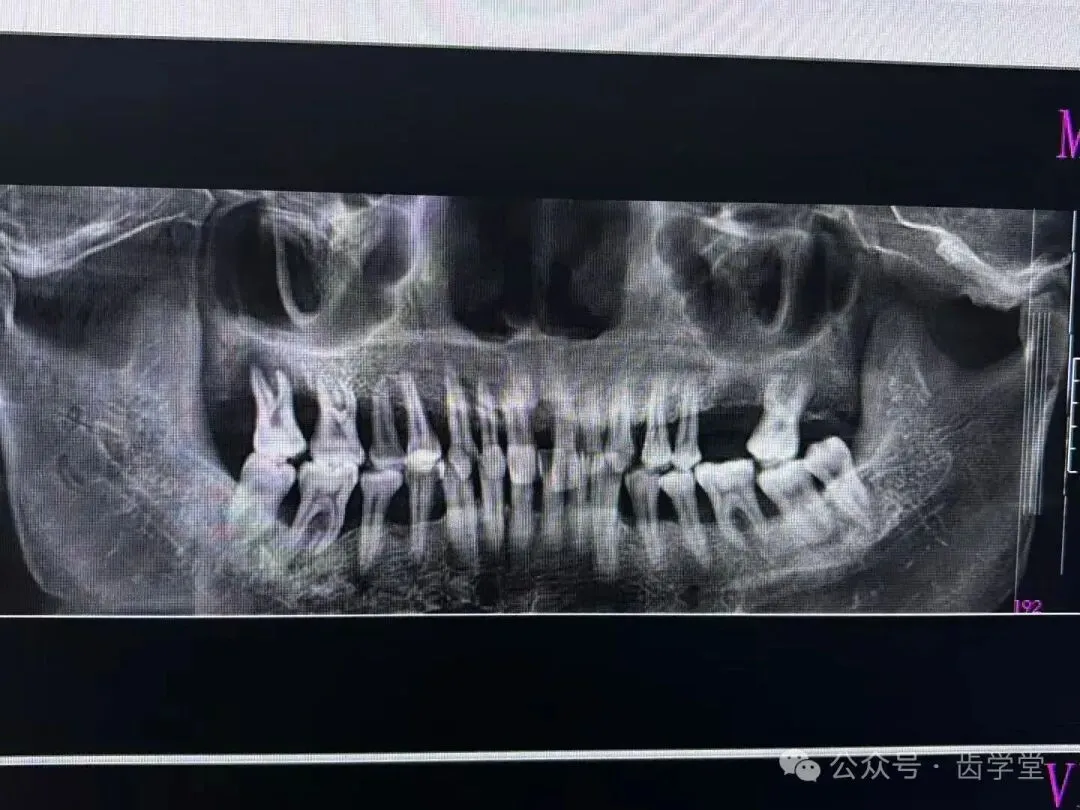

5. 自体牙移植的适应症和禁忌症及其把控;

8. 自体牙移植的术前检查、评估和准备;

13.受植位点不同情况移植的区别及其要点;